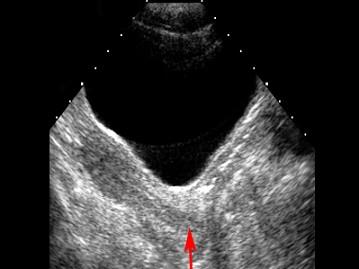

问题 红色箭头所指部位是 ( )

选项 A、膀胱 B、以上都不是 C、阴道 D、子宫 E、宫颈

答案 E